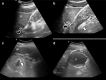

Methods: A plastic gastric phantom filled with water was created to mimic the gastric lumen and to test the operator's ability to recognize the capsule containing the balloon inside. In the clinical phase, we tested the operator's ability to recognize the swallowed capsule and its progressive filling in the gastric lumen by means of ultrasound in 36 consecutive patients with a mean body mass index of 35 in an outpatient setting.

Results: The ultrasound hyperechoic signal of the capsule in the gastric lumen was visible early on and was confirmed after the injection of a few milliliters of saline solution in the capsule with a cyst-like shape. The insertion of the balloon was successful in all cases at the first attempt, and the complete filling was monitored in real-time without the need for fluoroscopy. Postprocedure symptoms were limited to the first 24-48 h and were controlled by symptomatic therapy; endoscopic removal of the balloon because of painful distal gastric migration was necessary in one case after 3 months.

Conclusion: After a learning curve, we were able to demonstrate the placement of the balloon capsule inside the fundus of the stomach under ultrasound guidance without fluoroscopy in all patients in an outpatient setting.